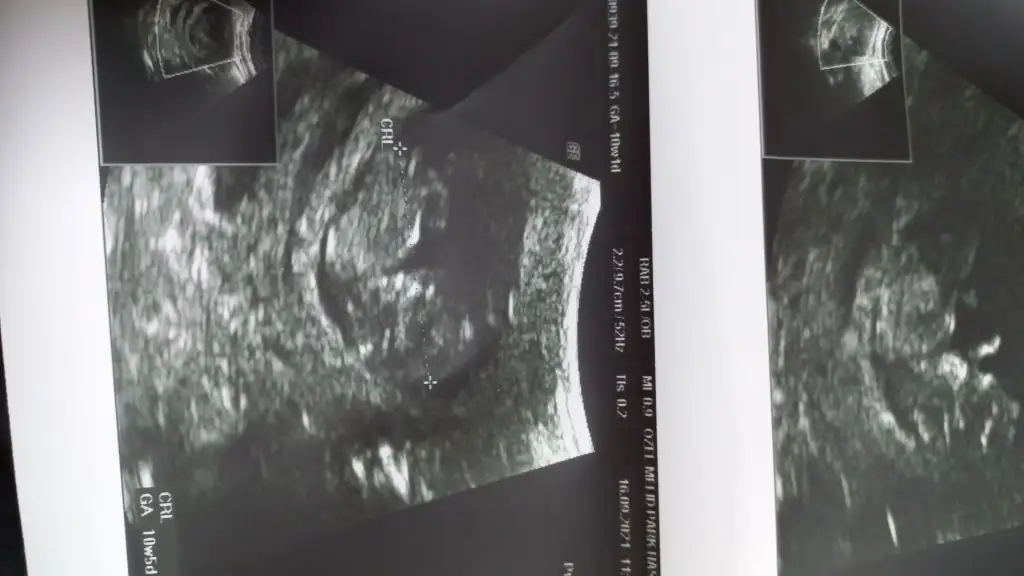

10+1 haftalık cinsiyet tahmini yapar mısınız:)